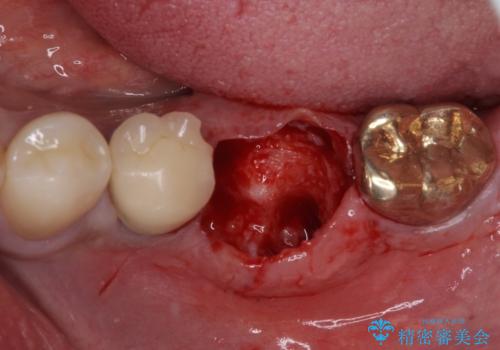

そのため、当院に新しく導入した手法により、抜歯をした日にインプラントを埋入し、そのままを仮歯を装着することで、他の歯への負担を軽減する計画を立てました。

インプラント埋入時に植立具合の安定性を測定したところ、十分な数値が得られたため、速やかに仮歯を装着して咬合回復をさせることができました。

抜歯を含めた外科処置を1回に抑えることができ、あっという間に治療を終えることができました。